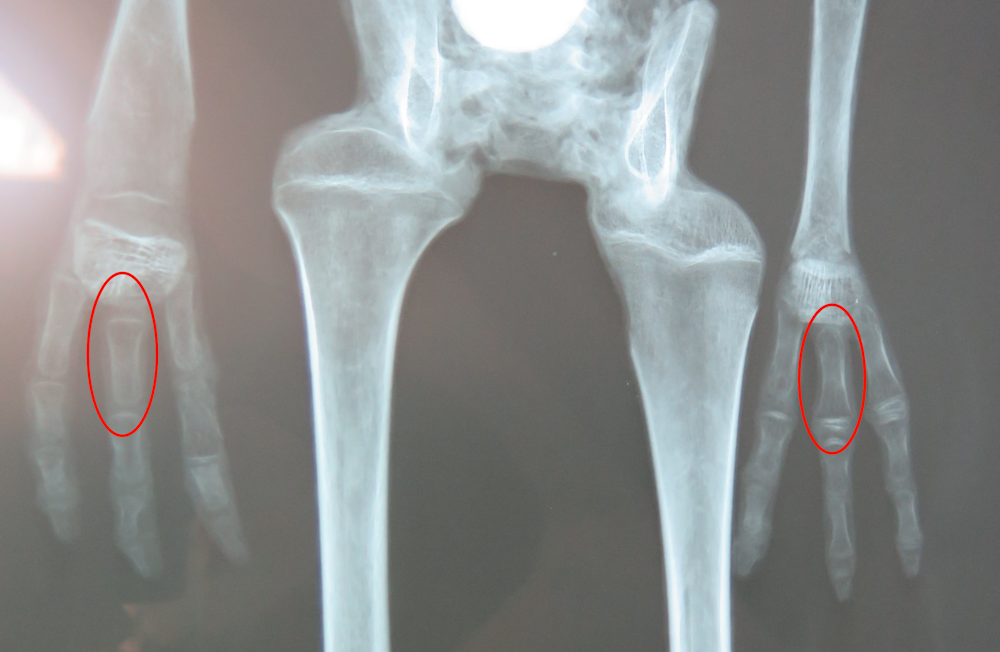

Thanks for your work. There are lots of smoking guns, any one of which destroys these mummies, but my favorite is Josephine's hands with the mixed up backwards fingerbones (two are highlighted below, X-ray taken from Antropogenez critical review).

On the Alien Project website where they have all the videos of scientists presenting this case to the Peru Congress in 2018, the first video is from the radiologist but they only talk about Maria and another case, not Josephine & Albert (the tiny aliens). The Scientists Against Myths video [timestamped] explains that Dr Korotkov, in his book and in correspondence, dismissed the x-rays as "not sufficient for any sound conclusions" although it's not clear if he's referring to the four hands, to Maria, or to the little aliens (or all of them).